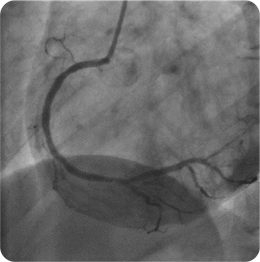

心筋梗塞を発症した際の冠動脈造影と治療後

血栓をカテーテルで吸引した上でバルーンにて拡張。更にステントを留置し、血流が再開しています。